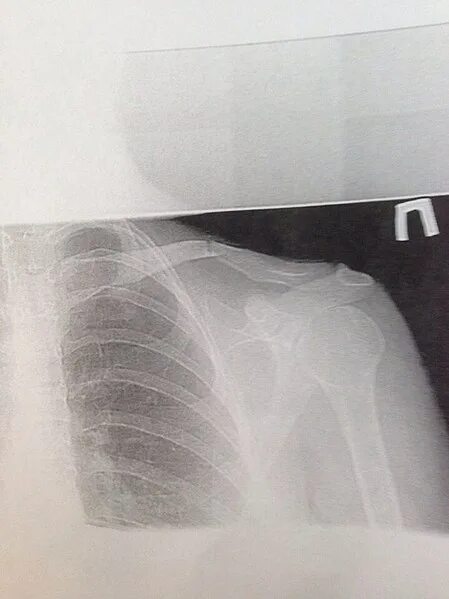

Сколько срастается ключица у детей